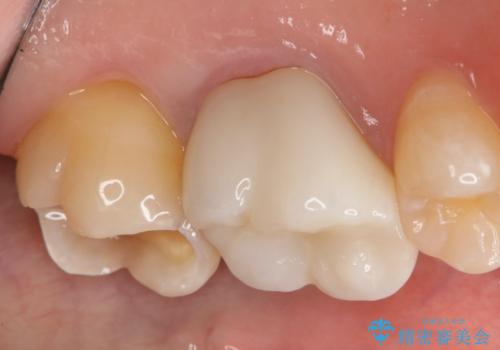

- 左上7番の銀歯をセラミックにやり変え希望の患者様です。

切削量・形態からセラミックインレーでの治療を計画しました。

銀歯とその直下のう蝕を除去した後、CRにて裏層しています。

インレー装着の際はラバーダムを使用しています。